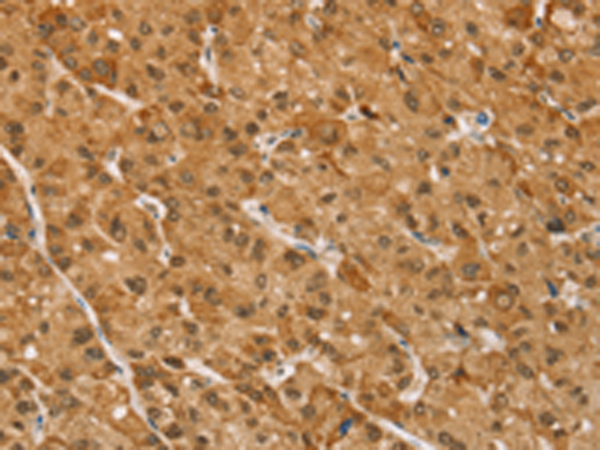

分类: 科研抗体货号: P08819别名: ST1B1; ST1B2; SULT1B2应用: WB,IHC反应种属: Human